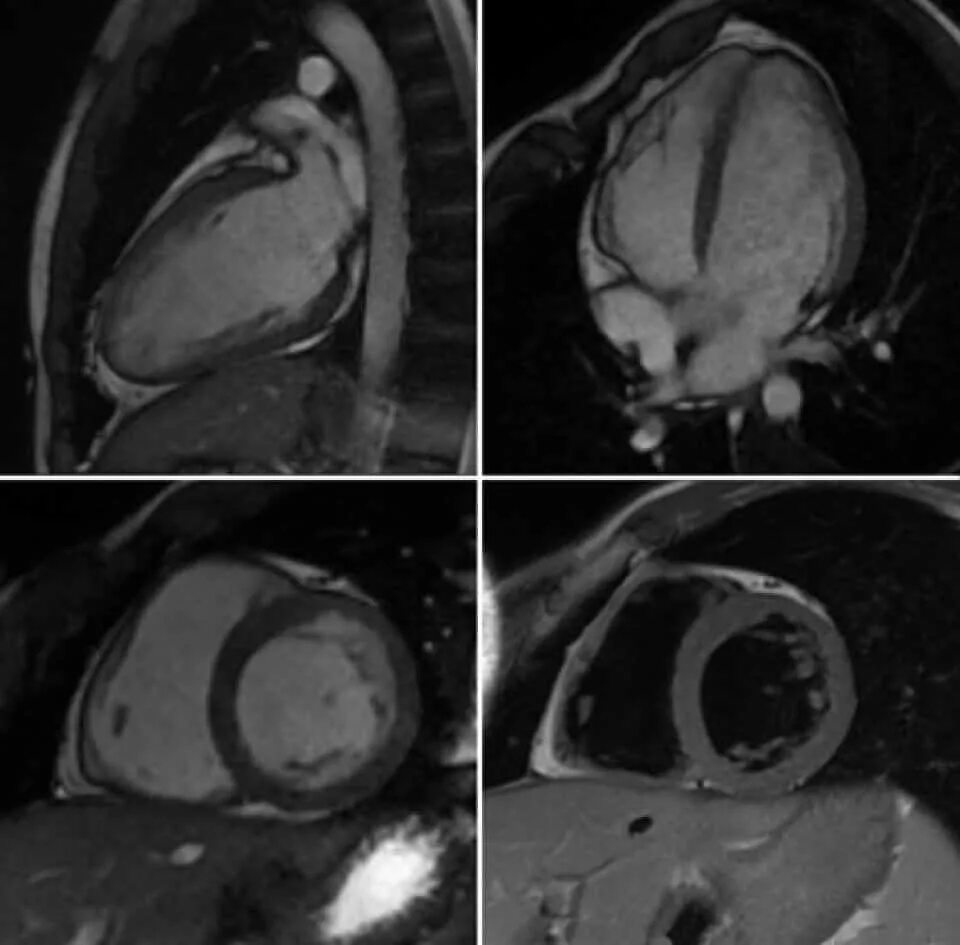

Как делают кт сердца